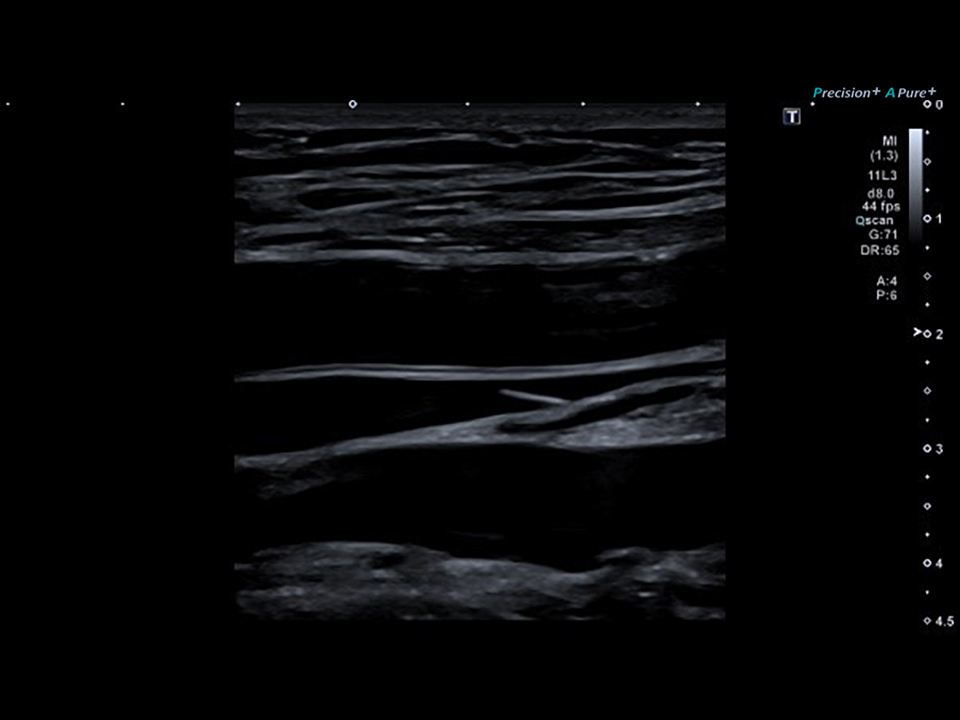

Peripheral Venous Color 11L3

Supraspinatus

Volare Plate

Peroneals

Calf Panoramic